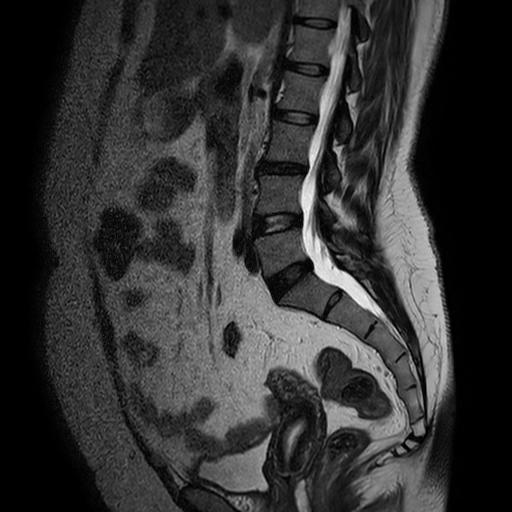

I developed MRI SEG Lite, a lightweight version of the original MRI-SEG software package, specifically tailored for resource-constrained environments such as the Raspberry Pi. This version is designed to perform automatic classification and segmentation of Spine MRI images directly on edge devices without reliance on high-end GPUs or cloud infrastructure.

To make this possible, the original deep learning model was converted and optimized using techniques such as model pruning, quantization, and format conversion (e.g., TensorFlow Lite), significantly reducing memory and compute requirements while preserving model accuracy to a similar level of the original one.

MRI SEG Lite supports the same core functionalities as the desktop version, including real-time visualization, but is optimized for environments with limited hardware resources and power constraints. This makes it suitable for use in remote clinics, field hospitals, or mobile diagnostic units.